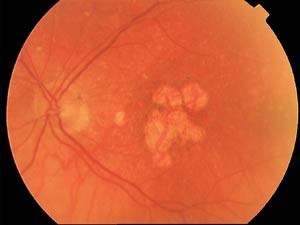

Neovaskularisering fra årehinnen kan foregå både bak pigmentepitelet (såkalt okkult neovaskularisering) eller bryte igjennom pigmentepitelet og ligge under nevroretina (kalt klassisk). Benevnelsene kommer fra utseende ved fluorosceinangiografi hvor pigmentepitelet ofte kan maskere patologiske kar. En «våt» aldersrelatert maculadegenerasjon kan redusere visus til fingertellingsnivå i løpet av 6 – 12 måneder, mens et øye med «tørr» variant sjelden fører til tap av tavlesyn i samme tidsperspektiv. En «utbrent» maculadegenerasjon har store arrdanninger sentralt i fundus, gjerne på grunn av blødninger som har oppstått i de patologiske kar (fig 4). Pasienter som merker defekter i sentralsynet og ev. forvrenging av synsbildet bør henvises til øyelege til vurdering.